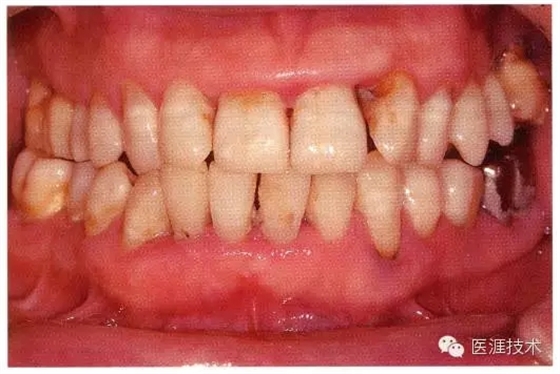

健康牙周組織的牙齦邊緣呈珊瑚粉,邊緣牙齦略呈圓弧狀。牙間可見三角形的牙間乳頭,牙齦邊緣相連呈貝殼形。

附著齦與游離齦相連時(shí),有時(shí)有游離齦溝存在(成人的30~40%)。

附著齦通過膠原纖維牢固結(jié)合骨骼與牙骨質(zhì),因此可見不可動(dòng)、硬而緊繃的點(diǎn)彩(橘皮樣點(diǎn)狀凹凸)。

從牙齦牙槽粘膜到根尖有牙槽粘膜。牙槽粘膜為暗紅色,與骨骼結(jié)合較松,故可動(dòng)。

健康且正常的牙周組織臨床圖像

50歲女性的健康口腔內(nèi)部

圖為50歲女性,無特殊全身疾病,不抽煙。持續(xù)保養(yǎng)6年。無填充物等問題,依照患者本人要求持續(xù)觀察。牙周組織臉頰側(cè)雖見部分萎縮,但X線牙片顯示牙間無骨吸收現(xiàn)象,保持著比較健康的狀態(tài)。